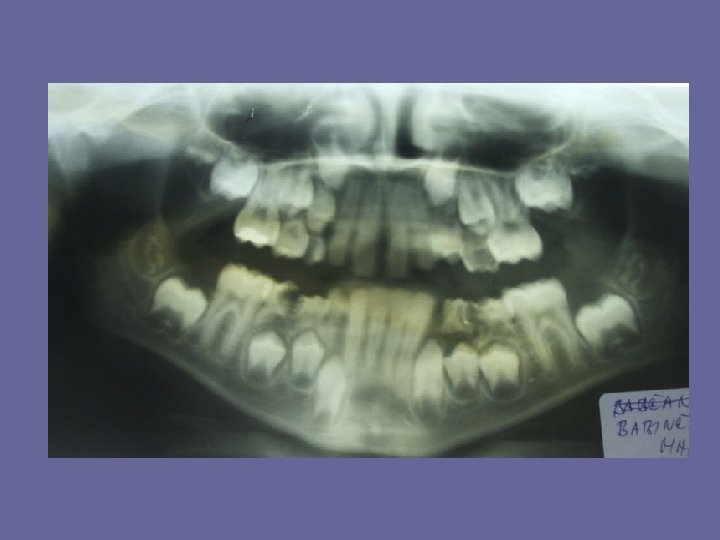

REPLACEMENT OF INCISORS

REPLACEMENT OF INCISORS • The permanent incisors develop lingual and palatal to the roots of deciduous incisors • The upper lateral incisors in their developmental position are overlapted by the central incisors. They escape as the central incisors erupt.

REPLACEMENT OF INCISORS The average difference in wide of the deciduous and permanent incisors is 7 mm in maxilla and 5, 5 mm in mandible. Space for these teeth, which are larger then their deciduous predecessors (particularly the uppers), is provided by: 1. utilization of existing spacing between the deciduous incisors 2. an increase in arch width takes place during the eruption of incisors. The amount of it is about 3, 5 mm in maxilla and 2, 0 mm in mandible. 3. an increase of length of dental arches, 2, 5 mm in maxilla and 2, 0 mm in mandible. 4. the permanent incisors are more proclined and thus form a larger arch than the deciduous incisors.

REPLACEMENT OF INCISORS While the lower primate spacings are important to allow arrangement of the first permanent molars in right relationship, the uppers provide the space for upper permanent incisors.

REPLACEMENT OF INCISORS • the deciduous dentitions without spacings (primate and between incisors) are liable to be replaced by crowded permanent dentition.

REPLACEMENT OF INCISORS • if there is not sufficient growth in arch width the lateral incisors may be trapped in their palatal position. • When the upper incisors erupt they are frequently distally inclined, there is a median diastema. This is due to the incisor roots being crowded mesially by the permanent canine crowns and should not be mistaken for a malocclusion. When the permanent canines erupt the median diastema will usually close.

REPLACEMENT OF INCISORS • When the lower incisors erupt they are often crowded but it is improve by further growth in arch width. • If the deciduous incisor root is not resorbed normally, the permanent incisor may be deflected lingually or palatally.

REPLACEMENT OF INCISORS The lower incisors erupt before the uppers. It causes the accelerated growth of mandible and the “ 2 th physiological reduction of overbite”.